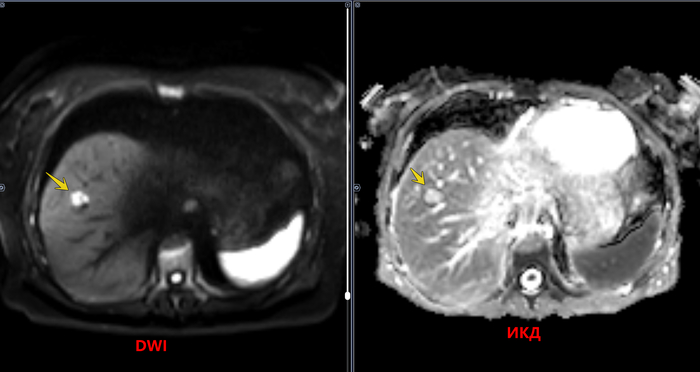

Структура печени неоднородная, за счет наличия в VIII сегменте правой доли дополнительного образования размерами 1,0х1,5х1,0 см, неправильной формы, с четкими неровными контурами, однородной структуры, повышенной интенсивности МР-сигнала в Т2 режиме, повышенного сигнала на высоких значениях b-фактора в режиме DWI и высокого сигнала на ADC-карте, с постепенным центрипетальным типом контрастирования. Заключение: МР картина образования (гемангиомы) правой доли печени.